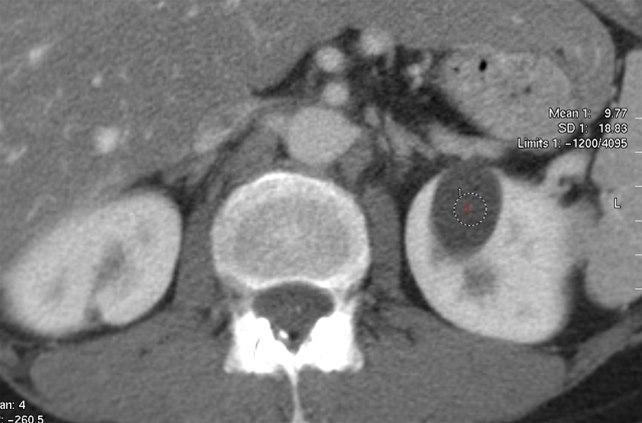

CT-bilde av nyrecysteSykdommen er arvelig, men selv om du har arvet de skadde arveanleggene (genene), så er ikke det ensbetydende med at du vil utvikle nyresvikt. Ved å studere arveanleggene har man funnet ut at det er to gener som kan være endret, og avhengig av hvilket gen som er skadet, skilles det mellom to hovedtyper (type 1-ADPKD - utgjør 85 prosent, type 2-ADPKD utgjør 15 prosent).

De avgjørende undersøkelsene er ultralyd eller CT hvor cystene kan påvises med sikkerhet. I tillegg tas blod- og urinprøver for å kartlegge nyre- og leverfunksjon. Ved mistanke om sykdom i blodårer kan annen bildediagnostikk være påkrevd.

Utviklingen (veksten) av nyrecystene kan følges med gjentatte ultralyd- eller MR-undersøkelser med års mellomrom. Det kan også bidra til å anslå når nyrefunksjonen blir så påvirket at behandling er nødvendig.